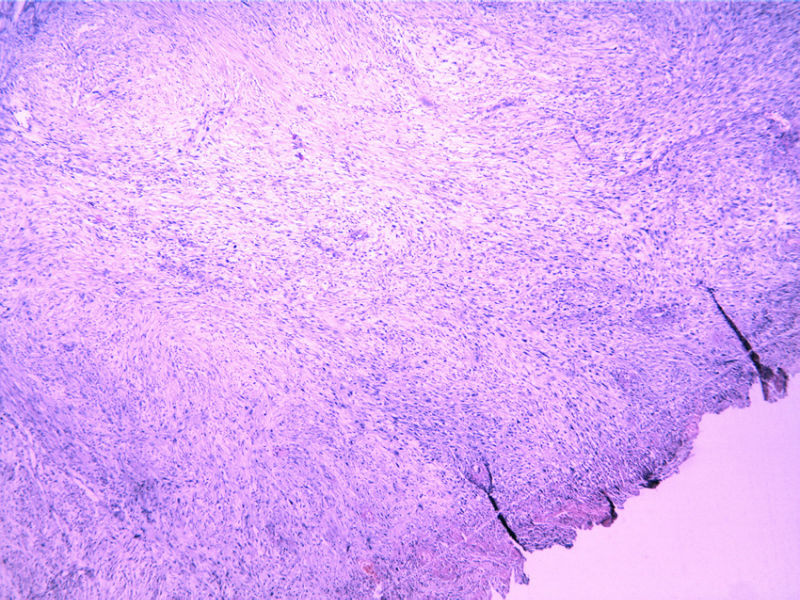

瞧这个小腿肿物,再看IHC(48Y,V2X1X1cm)

• 瞧这个小腿肿物,再看IHC(48Y,V2X1X1cm)图1

图1

梭形细胞肿瘤。倾向为低度恶性神经源性肿瘤,平滑肌、纤维肌纤维母细胞、组织细胞来源肿瘤鉴别。

低度恶性肿瘤,首先考虑MPNST,其次为纤维母细胞性肿瘤,需要做标记。

蒙一个诊断,有淋巴细胞浸润考虑神经鞘。

梭形细胞肿瘤病史不详细,病史短的可见结节性筋膜炎,这可是一个大陷阱,时刻要想着它,时间很长者要考虑神经鞘可能,是否恶性也只限于局部复发问题不是很大,。如果是成年人近期又生长很快的肿块粘液样纤维瘤就不能排除了,而且一定是低度恶性的。仅根据病程就有这么多鉴别,如果结合免疫组化需要鉴别的就更多。所以提供的线索不多只能叫猜诊断。